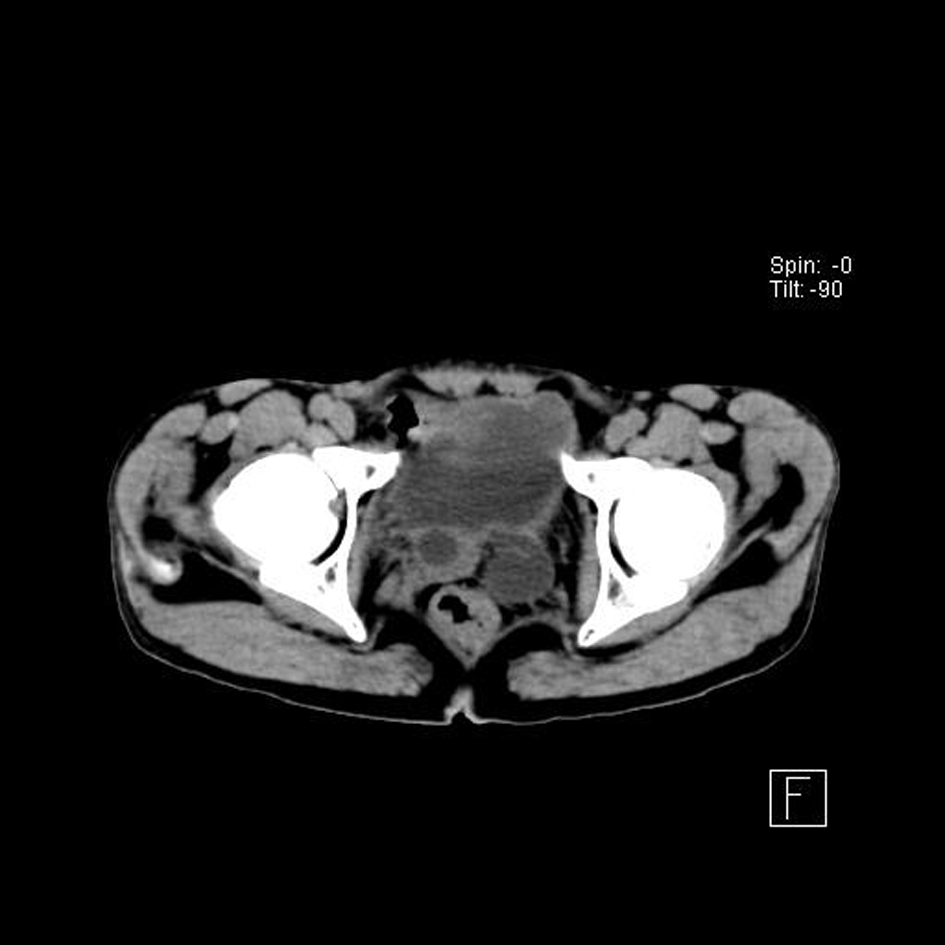

Ultrasonograph of abdomen revealed bilateral hydroureteronephrosis with hardly any parenchyma on left side with ectopic opening of ureters in the proximal prostatic urethra. TRUS examination showed non-visualized left seminal vesicle in addition to the above findings. Non-contrast CT (Fig. 1-3) and MRI showed the anatomical details but no ureterocele was reported. No vesicoureteric reflux was seen in the voiding cystourethrogram film.

![]() Click for large image | Figure 2. Dilated ureters posterior to bladder neck. |